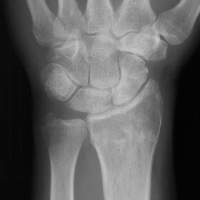

| Case 6 Extraarticular distal radius fracture with angulation and dorsal comminution. |

| Attempts at

closed reduction alone were unsuccessful. |

| Late result. |